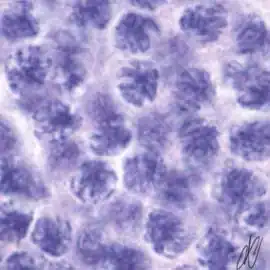

Reproduction - Testis

Normal Histology

spermatogenesiscysts with successive stages of spermatogenesis in a seminiferous tubule | |||

| H&E | Putt's carbol fuchsin as a marker of spermatogenic maturation |